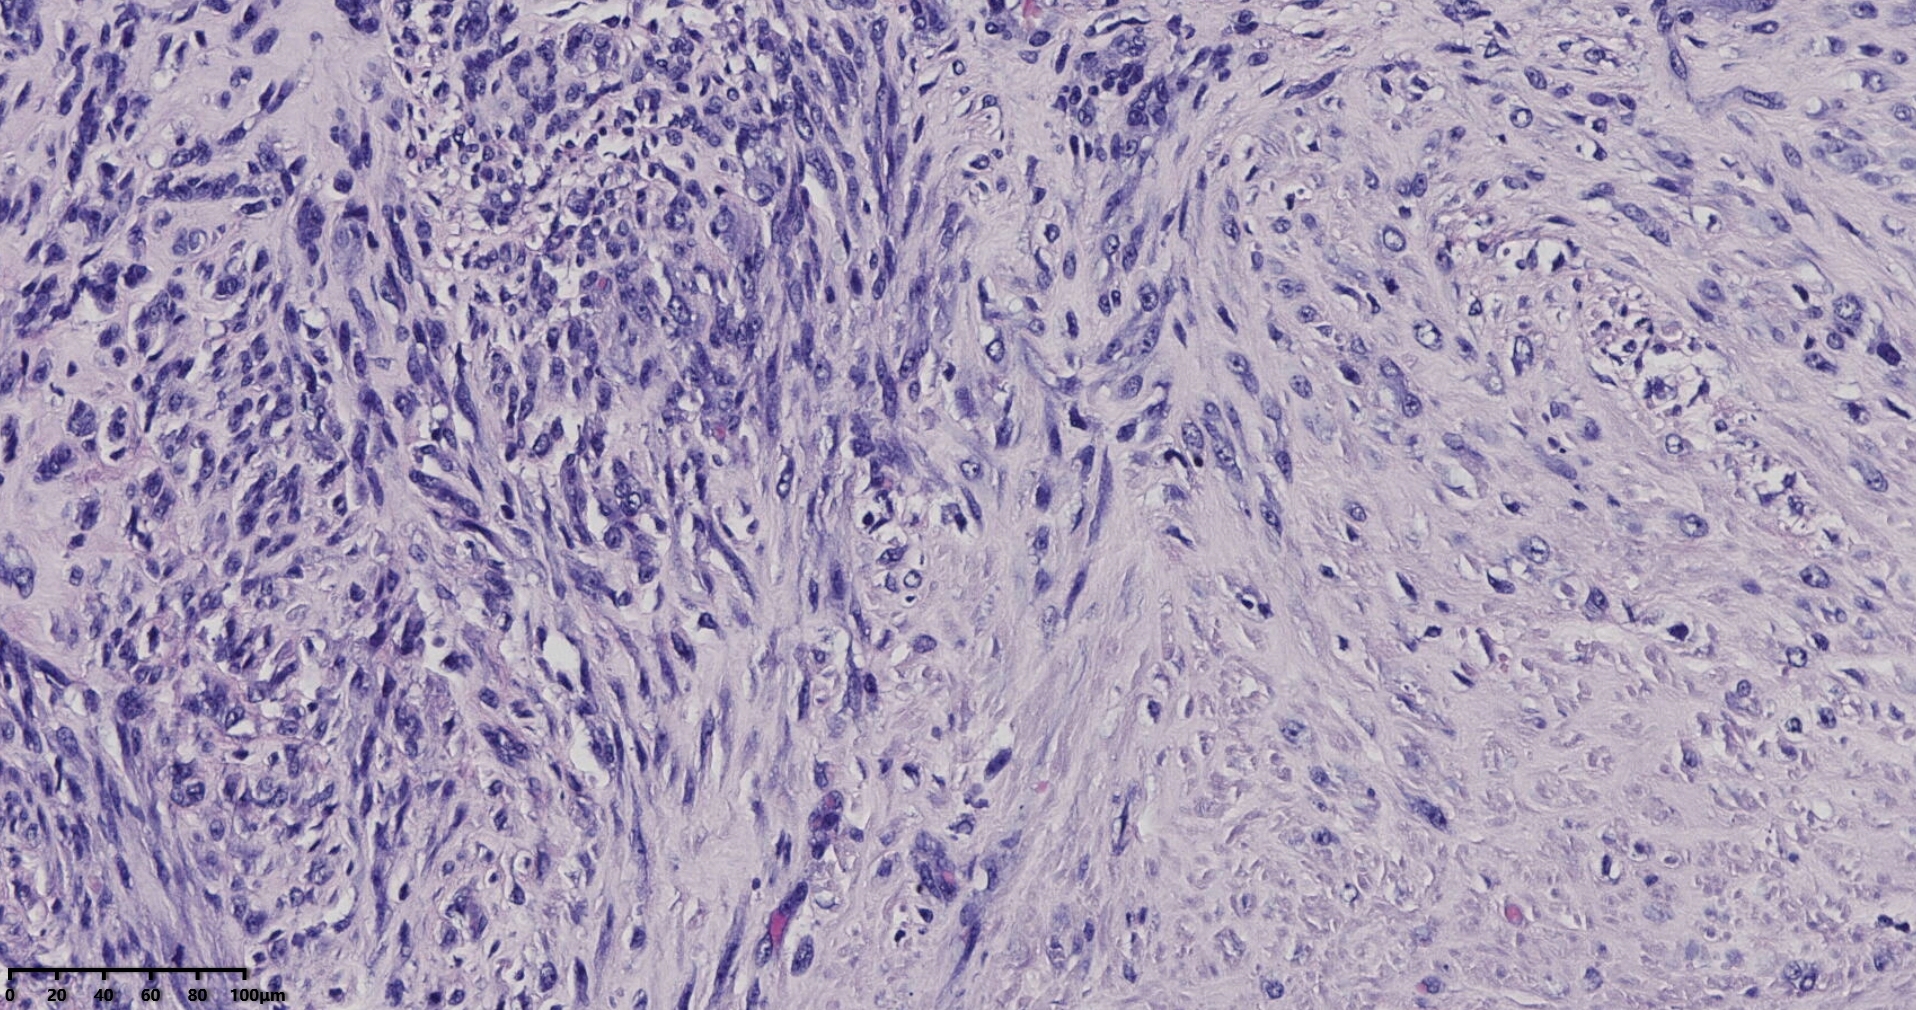

镜下所见小肿物无特殊,大肿物瘤细胞密集,中心区有变性、坏死,瘤细胞核有异型性。大肿物补充取材,发现,部分区域切面灰黄,这个区域,瘤细胞更密集,异型性更显著。肿物边缘有薄层正常平滑肌组织被覆,靠近边缘瘤细胞最密集,局部瘤组织内小血管较丰富。

会诊:考虑平滑肌肉瘤。

北医三院会诊:子宫平滑肌瘤伴红色变性可能性大,建议加做免疫组化及NGS检测进一步明确诊断。